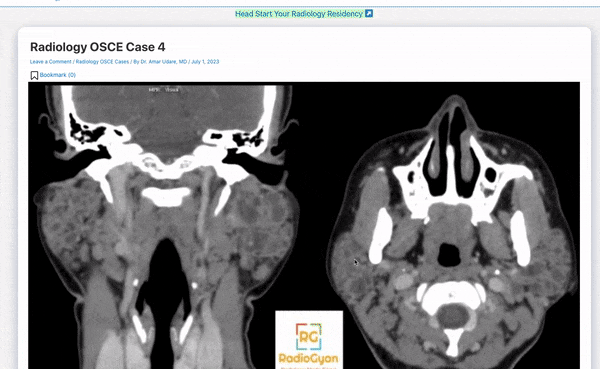

An example Radiology OSCE case is shared below.

You can check out more such Radiology OSCE cases on this page: